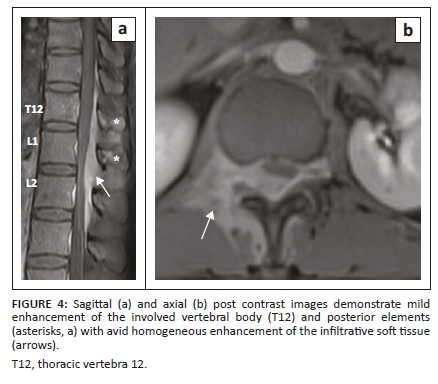

The MRI examination revealed altered signal intensity involving the bodies and posterior elements of the T12 vertebra and L1 vertebra which showed hypointense signal on T1 weighted (T1W) and hyperintense signal on T2W and short tau inversion recovery (STIR) sequences (Figures 1 and 2) with mild enhancement on post contrast images. On chemical shift imaging, the involved vertebral body did not show reduction in signal on opposed phase images (Figure 3). There was a homogeneously enhancing soft tissue mass in the posterior epidural space extending from the T12 to L2 vertebral levels appearing isointense on T1W and hyperintense on T2W and STIR images (Figures 2 and 4). The lesion caused narrowing of the spinal canal with marked compression of the conus medullaris and cauda equina nerve roots. There was associated widening of bilateral neural foramina (right > left) at the T12-L1 and L1-L2 levels, with infiltration of the soft tissue lesion into bilateral paraspinal muscles. A possibility of myeloid sarcoma was suggested given the clinical profile and imaging findings.

A precise and prompt diagnosis of chloroma is crucial as it allows the institution of definitive radiotherapy or adjuvant chemotherapy for local control of the disease, which helps in relieving cord compression and obviates any unnecessary surgery. Magnetic resonance imaging forms the cornerstone in the evaluation and diagnosis of spinal involvement in chloroma by aiding in spatial localisation (i.e. vertebral, epidural, intradural extramedullary and intramedullary), determining its extent and assessing the degree of cord compression, if present. At MRI, vertebral involvement in chloroma manifests as focal, multifocal or diffuse leukaemic infiltration of the vertebral marrow with low signal intensity on T1W, high signal intensity on T2W images and avid enhancement on post contrast images. Chemical shift imaging remains a useful entity when differentiating this condition from red marrow conversion. A propensity for ligamentous and subperiosteal involvement is also seen as a result of spread via the haversian canals.6 However, this non-specific appearance can be confused with marrow infiltrating disorders such as multiple myeloma and lymphoma; hence, a thorough clinical history of haematological disease is imperative in establishing the diagnosis.

Epidural involvement in chloroma can often occur in conjunction with vertebral body involvement. These often present as multiple masses which may be either contiguous or discrete, involving different vertebral levels. They usually show isointense and intermediate signal on T1W and T2W images respectively, with homogeneous post contrast enhancement.7,8 Central non-enhancing necrotic areas may be identified and diffusion restriction may be noted on diffusion weighted images. The lesions can cause effacement of the epidural fat with inward displacement of the dura mater and compression of the spinal cord with partial or complete obliteration of the cerebrospinal fluid (CSF) space. Frequent association with compressive myelopathy or neuronopathy, regardless of lesion location, is also seen. The combined intra-extraspinal form of chloroma, with a resultant 'dumb bell configuration', may simulate the appearance of a nerve sheath tumour on imaging. In such scenarios, absence of intense T2 hyperintensity without secondary bony changes (destruction or remodelling) favours chloroma.4